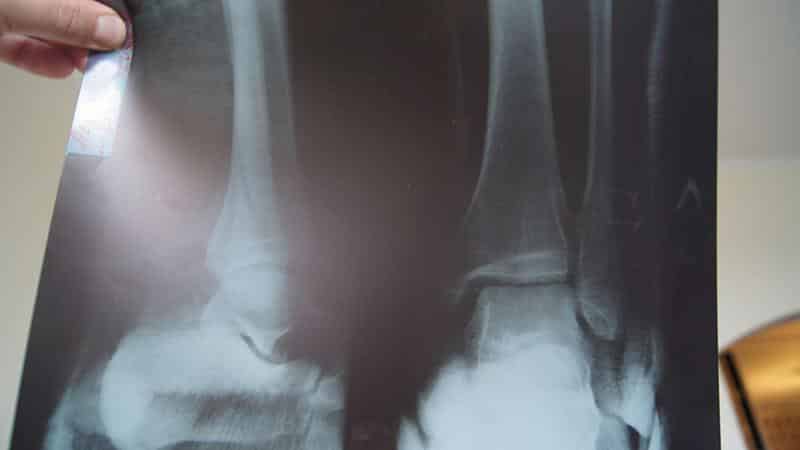

| Рентгенологическая картина | Полное сращение костных отломков, наличие костной мозоли, восстановление кортикального слоя | Неполное сращение или отсутствие сращения костных отломков, отсутствие или недостаточное количество костной мозоли |

Как только пациент сообщает о таких симптомах, врач повторно проводит обследование с использованием рентгеновского аппарата. Если осложнения действительно имеют место, на рентгеновских снимках можно заметить небольшое пространство между отломками поврежденной кости, что указывает на слабую консолидацию перелома.